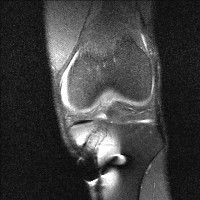

무릎 mri 간단히 봐주실 수 있으시나요 ㅠㅠ

안녕하세요 8년전 십자인대 수술하고 최근 무리한 운동에 무릎 불편감이 생겨서

mri 찍었습니다.

진단결과는 첫 찍은 병원에서 활액막염 이라는 진단을 받았습니다. 혹시 봐주실 수 있으실까요?

• 안녕하세요. 강성주 의사입니다.

올라온 MRI가 단편적이라서 정확한 진단에 어려움이 있지만 십자인대에는 큰 이상이 있지는 않은것 같으며, 무릎관절내 물이 있는 것으로 보아 활액막염의 진단이 맞을 것 같습니다.

하지만 단편적인 영상이기 때문에 촬영병원에서 정확한 판독지 등을 받으시는 것이 좋겠습니다.